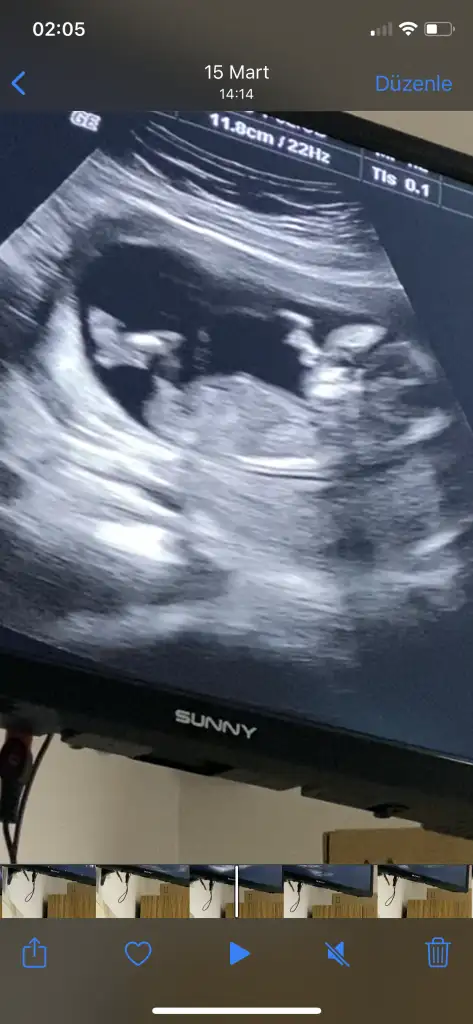

herkes sağolsun gerçekten sıkıldıkça insan buraya giriyor fikir alıyorErkek sankiEki Görüntüle 2807800 Kızlar bizede tahmin de bulunur musunuz

Doktorumuzda çıkıntıya göre erkek gibi ama kordonda olabilir demişti netleşince yazarımErkek sanki